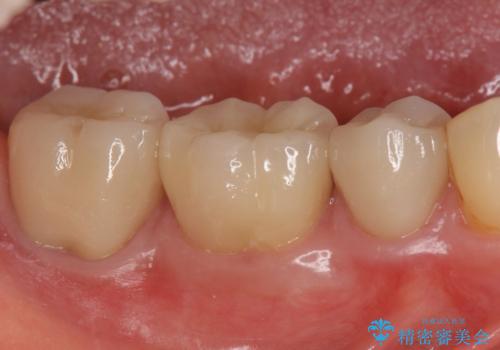

- 右下奥の銀歯3本をオールセラミッククラウンで治療した症例です。

今回用いたオールセラミッククラウンは、ジルコニアフレームという白い素材の上にセラミックを盛っているため審美性が非常に高いのが特徴です。

またジルコニアは人工ダイヤモンドの材料にも使われているほど高い強度を持っており、そのためオールセラミッククラウンは審美性だけでなく、奥歯やブリッジの補綴も可能とするクラウンです。